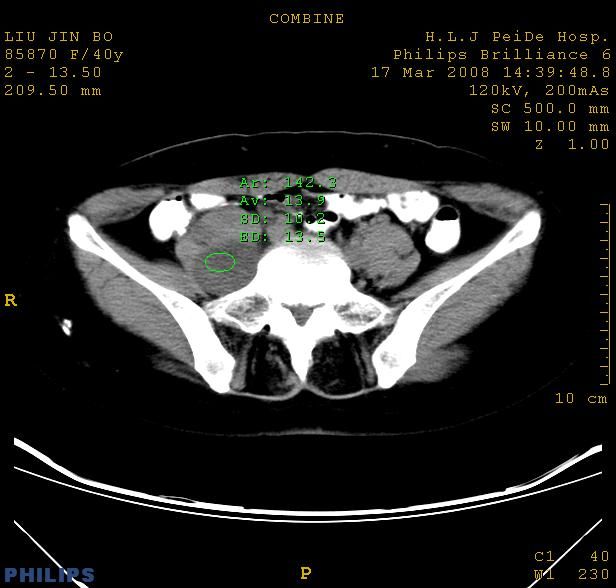

以下是引用qiuleiyu在2008-4-27 12:36:00的发言:[br]支持;右侧腰大肌后方神经源性肿瘤可能大,神经节细胞瘤?

以下是引用形影不离在2008-4-27 14:11:00的发言:[br]1.考虑右侧腰大肌脓肿。[br]2.左侧附件区炎症。[br]3.子宫增大,建议:进一步检查。